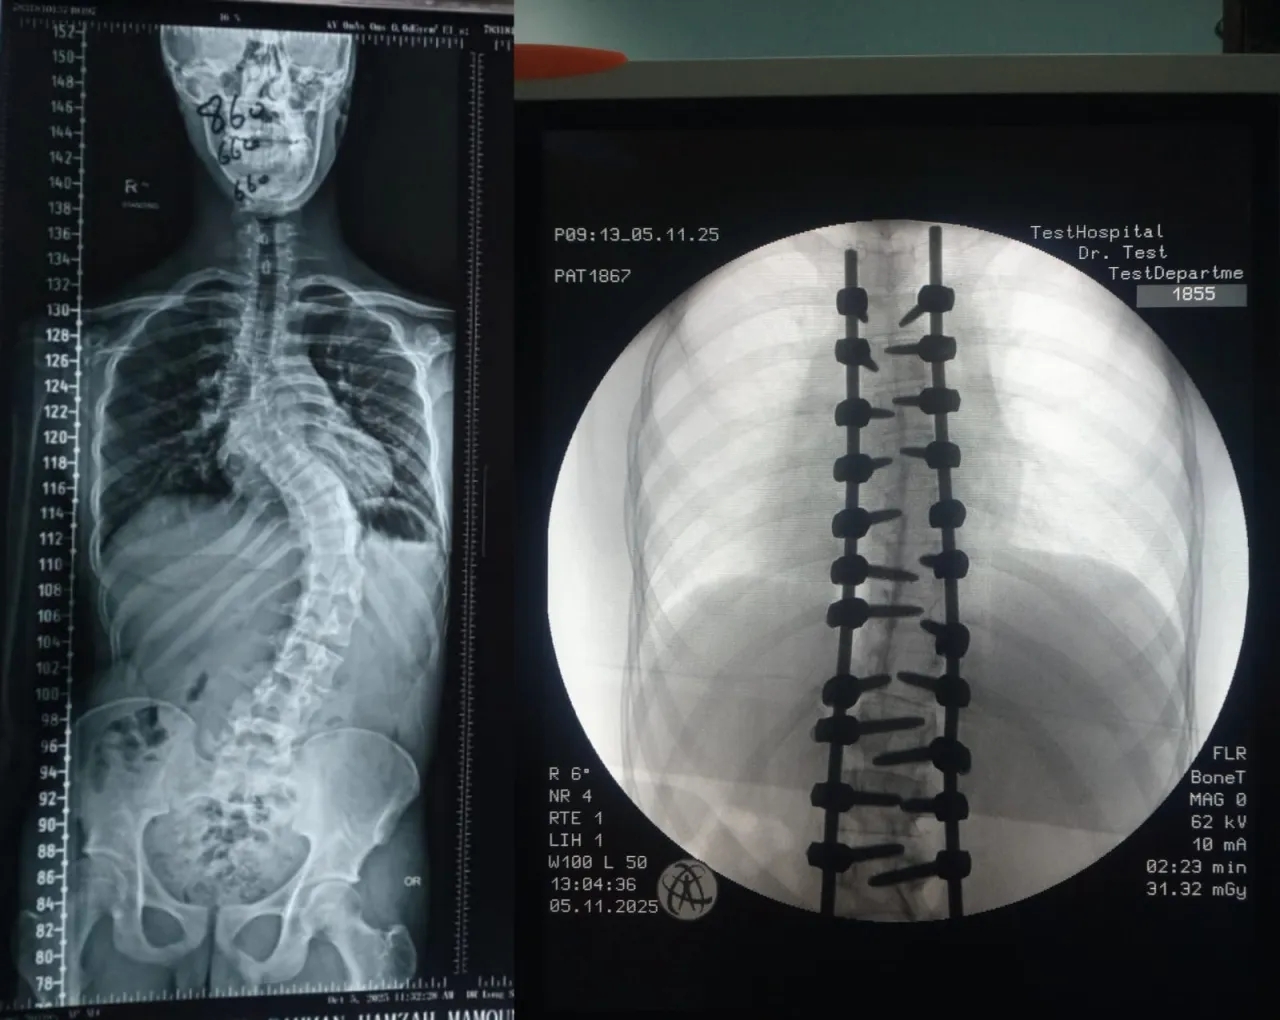

إنجاز طبي في مستشفى الأمير حمزة: تصحيح جنف حاد بالعمود الفقري

الوقائع الإخباري: شهد قسم جراحة العمود الفقري في مستشفى الأمير حمزة إنجازًا طبيًا مميزًا تمثّل في إجراء تدخّل جراحي معقّد لتصحيح جنف العمود الفقري لدى أحد المرضى الذين يعانون من تشوّه حاد في الفقرات.

وقد أُجريت العملية باستخدام جهاز الملاحة الجراحية المتقدّم، الذي أتاح دقةً عالية في التعامل مع التشوّهات البنيوية الشديدة، وسهّل توجيه الأدوات الجراحية ضمن المسار الآمن والمثالي.

كما اشتملت العملية على إزالة أجزاء محددة من الأطراف الخلفية للفقرات لتحقيق التصحيح المطلوب واستعادة التوازن والمحاذاة الطبيعية للعمود الفقري.